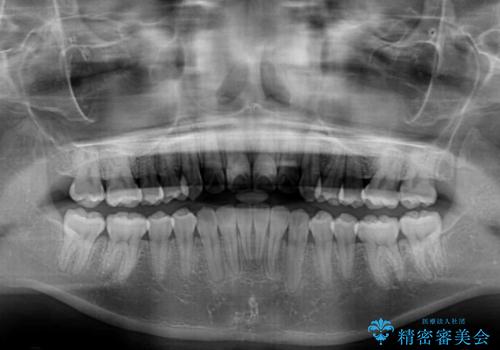

マウスピース矯正は毎日しっかりと装着することがとても大切です。

こちらの方はしっかりと指示を守って装着してくださったため、予定通り治療を終えることができました。